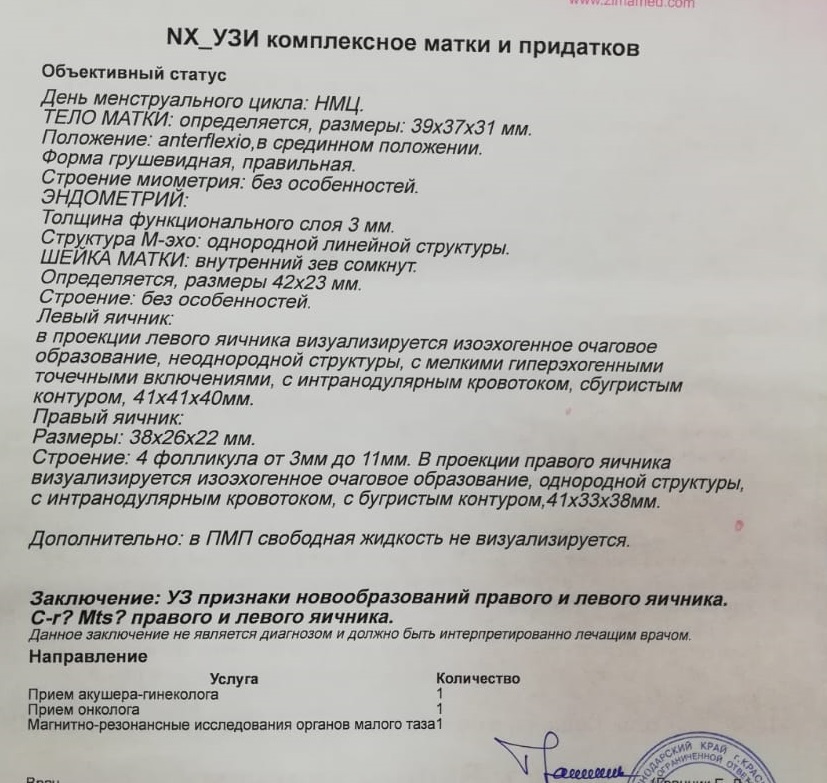

КТ диагностика тубоовариального абсцесса: Подходы и изображения

Раздел: Объективный взгляд